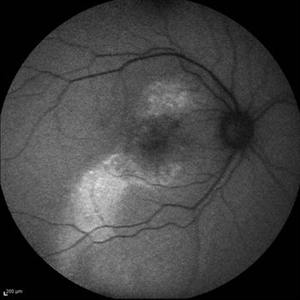

Best Disease Best DiseaseMar 9 2013 by Hamid Ahmadieh, MD Autofluorescence Imaging of the left eye of a 49-year-old man with decreased VA due to advanced Best disease. Photographer: Soodabeh Fooladin, Negah Eye Center, Tehran Imaging device: Heidelberg Spectralis Condition/keywords: autofluorescence imaging, Best disease